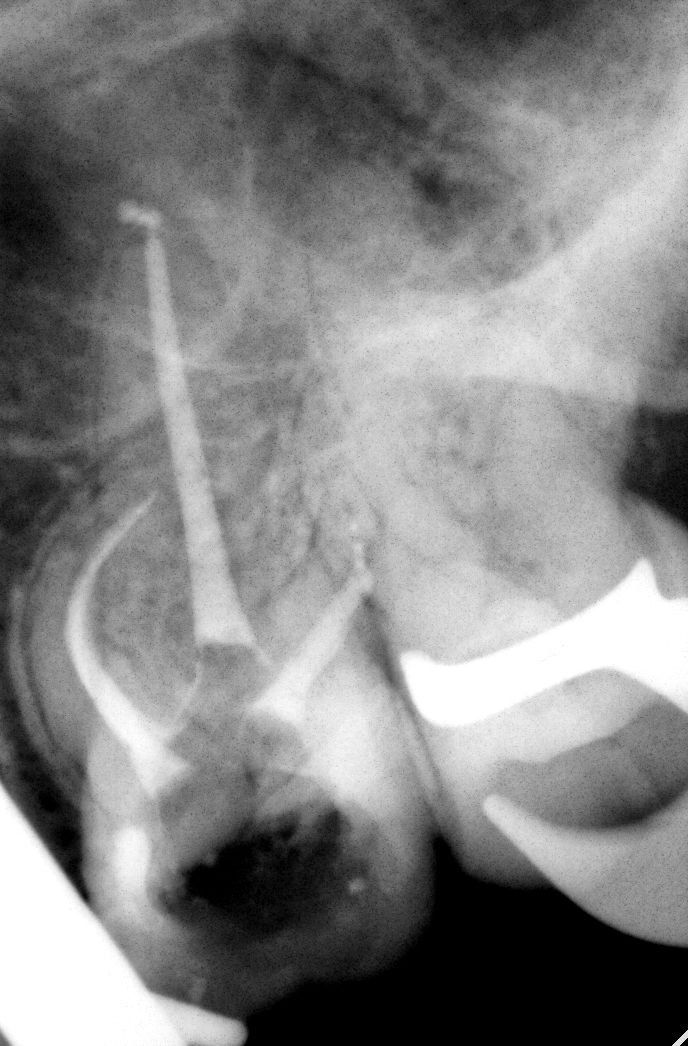

Первое, что нужно сделать — попробовать байпас. Если вы работаете с бинокулярами, можно пробовать байпас даже когда обломок застрял в средней трети. если обломок тонкий или каналы сходятся, в канале практически всегда найдётся пространство, чтобы его обойти. И это гораздо безопаснее для зуба, чем сразу хвататься за ультразвуковую насадку.

Байпас не удался, а периапикальный очаг присутствует. Здесь нужно оценить: можно ли безопасно извлечь обломок? Ультразвук? Апикальная хирургия? Если да — извлекаем. Если нет — обломок лучше оставить. Потому что даже при наличии очага и оставленного фрагмента уровень заживления составляет порядка 80%. А вот агрессивное извлечение может значительно ухудшить реставрационный прогноз зуба.